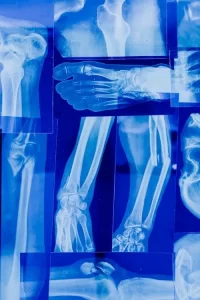

Los Rayos X utilizan radiación en forma de ondas electromagnéticas para capturar imágenes de los tejidos y estructuras internas del cuerpo. Son especialmente útiles para examinar huesos y dientes. Dependiendo de la parte del cuerpo a estudiar, el proceso puede variar ligeramente.